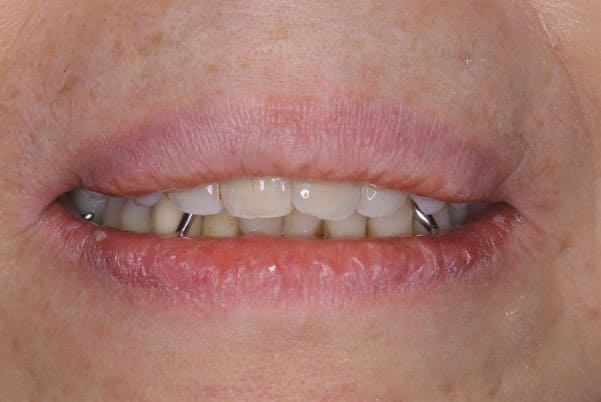

上前歯はブリッジの差し歯により根が折れ炎症を起こしお痛みのある状態でした。

原因は長期使用により下の義歯の歯が削れたことにより、下前歯が上前歯を突き上げ強い力が加わっていたことが根本的な原因と考えられます。

治療前は、奥歯が下がり、かみ合わせが乱れています。適切な入れ歯はそのままのかみ合わせで義歯を作るのではなく治療後のように、前歯から奥歯までのラインが真っすぐ揃った、かみ合わせの面を適切に付与し、よく咬め、残りの歯に負担がかからないかみ合わせとしました。

とにかく何も食べられないこと、人に会えないことから、なるべく早く何とかしたいとのご希望でした。

患者様とご相談の上、まず早急に上記を回復させるため、初診含め3度の来院でお食事ができ、見た目を回復できるように治療用義歯を作製、装着しました。

本来は、数本の上前歯の折れてしまって残せない歯は抜いてから歯肉の治癒を待ち、数か月後に型どりから作製になりますが、抜歯即時義歯といって、歯を抜く前に型、かみ合わせをとり、抜歯を行ったその日に上下の義歯を装着する特殊な治療法を用いたことで、10日後には治療用義歯をお口に装着することができ、お痛みもなくお食事ができ、ご友人とのお食事にも行けることが可能になりました。

本来、入れ歯作製は技工所と言って、義歯を作製する所に発送するため、作製には時間がかかりますが、院内に技工専用スペースを完備しており、長年、義歯治療において、技工も技術の習得してきましたので技工士さんではなく、かみ合わせの道具も私自身で院内で作製したことで、初診日の次の日にご来院いただきかみ合わせを採ることで、診断、型どり、かみ合わせ、装着まで10日という最短のご希望にこたえらた方です。

お写真は治療用の仮の入れですが普段通りお食事ができるとのことで少し食べ物もついています。。。